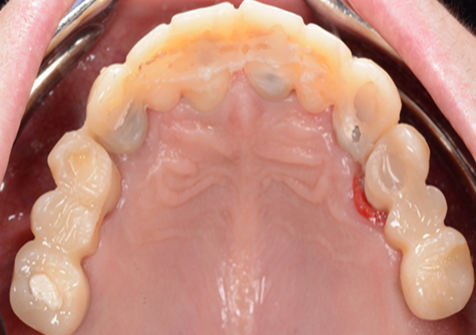

Clinical case: Extraction of all teeth in upper maxilla,

immediate implant placement, & provisionalization

- Courtesy of Dr. Iulian Filipov, Romania -

Keywords

AnyRidge, immediate placement, immediate provisionalization, maxillary fully edentulous case, initial stability, edentulous, Dr. Iulian Filipov, R2GATE, MEGA ISQ

Products:

AnyRidge implant system, Mega ISQ, R2GATE